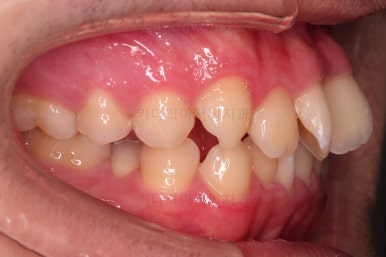

초진 시, 입안의 모습입니다.

치아를 모두 담기에 골격이 매우 작았어요.

이런 경우 치열이 ㅃ뚤어지거나 입이 튀어나오거나 뻐드렁니가 되거나 특정 치아가 묻혀버리거나 맨 뒤치아가 마치 사랑니처럼 올라오지 못한다거나 등등의 문제가 생기는데요.

이번 환자분은 전반적으로 삐뚠 상황이었어요.

앞니도 대칭적으로 삐뚤어져 흔히 나비치아라고 하는 형태로 보이고, 아랫니들은 U자 아치의 형태가 찌그러져 있네요.

당연히 교합도 맞지 않고요.

위턱, 아래턱이 모두 작은 형태였고 특히 아래턱이 작아 약간의 돌출된 느낌을 주지만 이런 경우 입을 무작정 많이 넣는게 답은 아닙니다.

웃거나 말할 때 드러나는 치열의 느낌은 가지런하지 못해 심미적으로 좋지 못하고요.